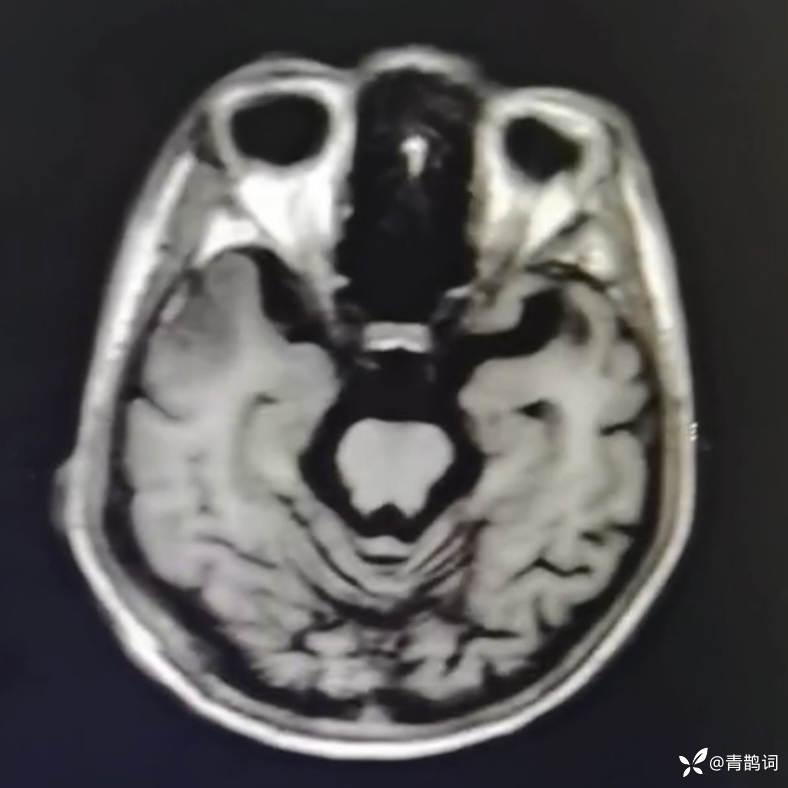

乐痴于医等 2人推荐简要病史:42岁男性,记忆力下降及听力下降一年余。既往体健,否认前驱感染病史。否认家族史。三个月前就诊于当地医院,自述腰穿脑脊液乳酸增高。现就诊于我院,查体记忆力下降,计算力下降,定时定向差,吟诗样语言。完善磁共振如下:

FLAIR: